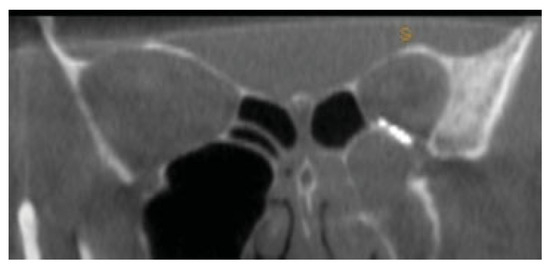

Figure 3.

Sagittal section of posterior orbital floor defect in case 1.